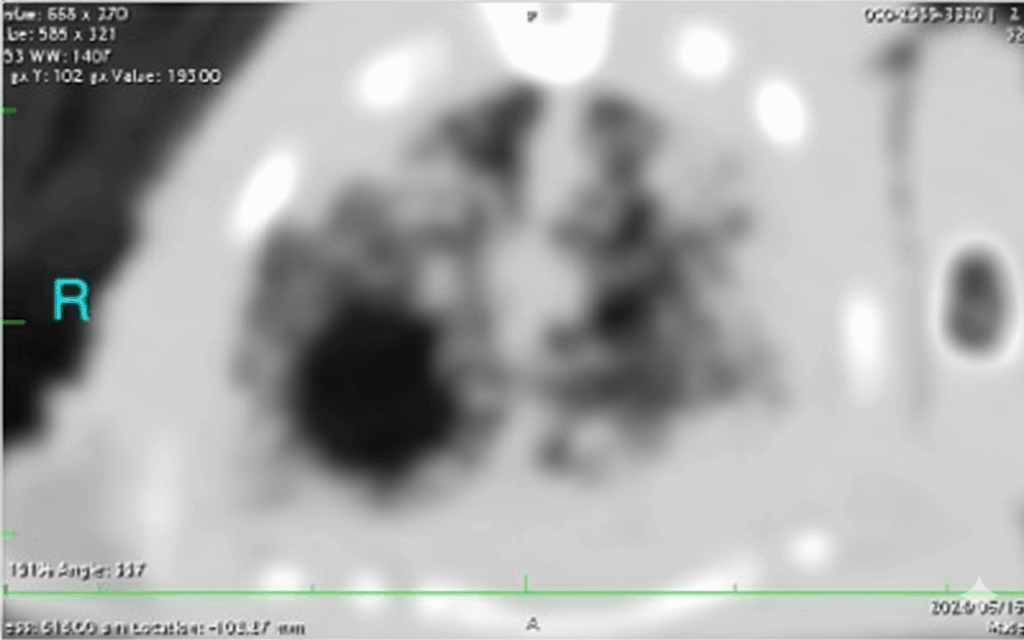

CT検査は、X線では評価が難しい初期病変や、肺実質の詳細な病変(例:微小な膿瘍、真菌症の病巣)を特定する上で、極めて優れた診断情報を提供します。